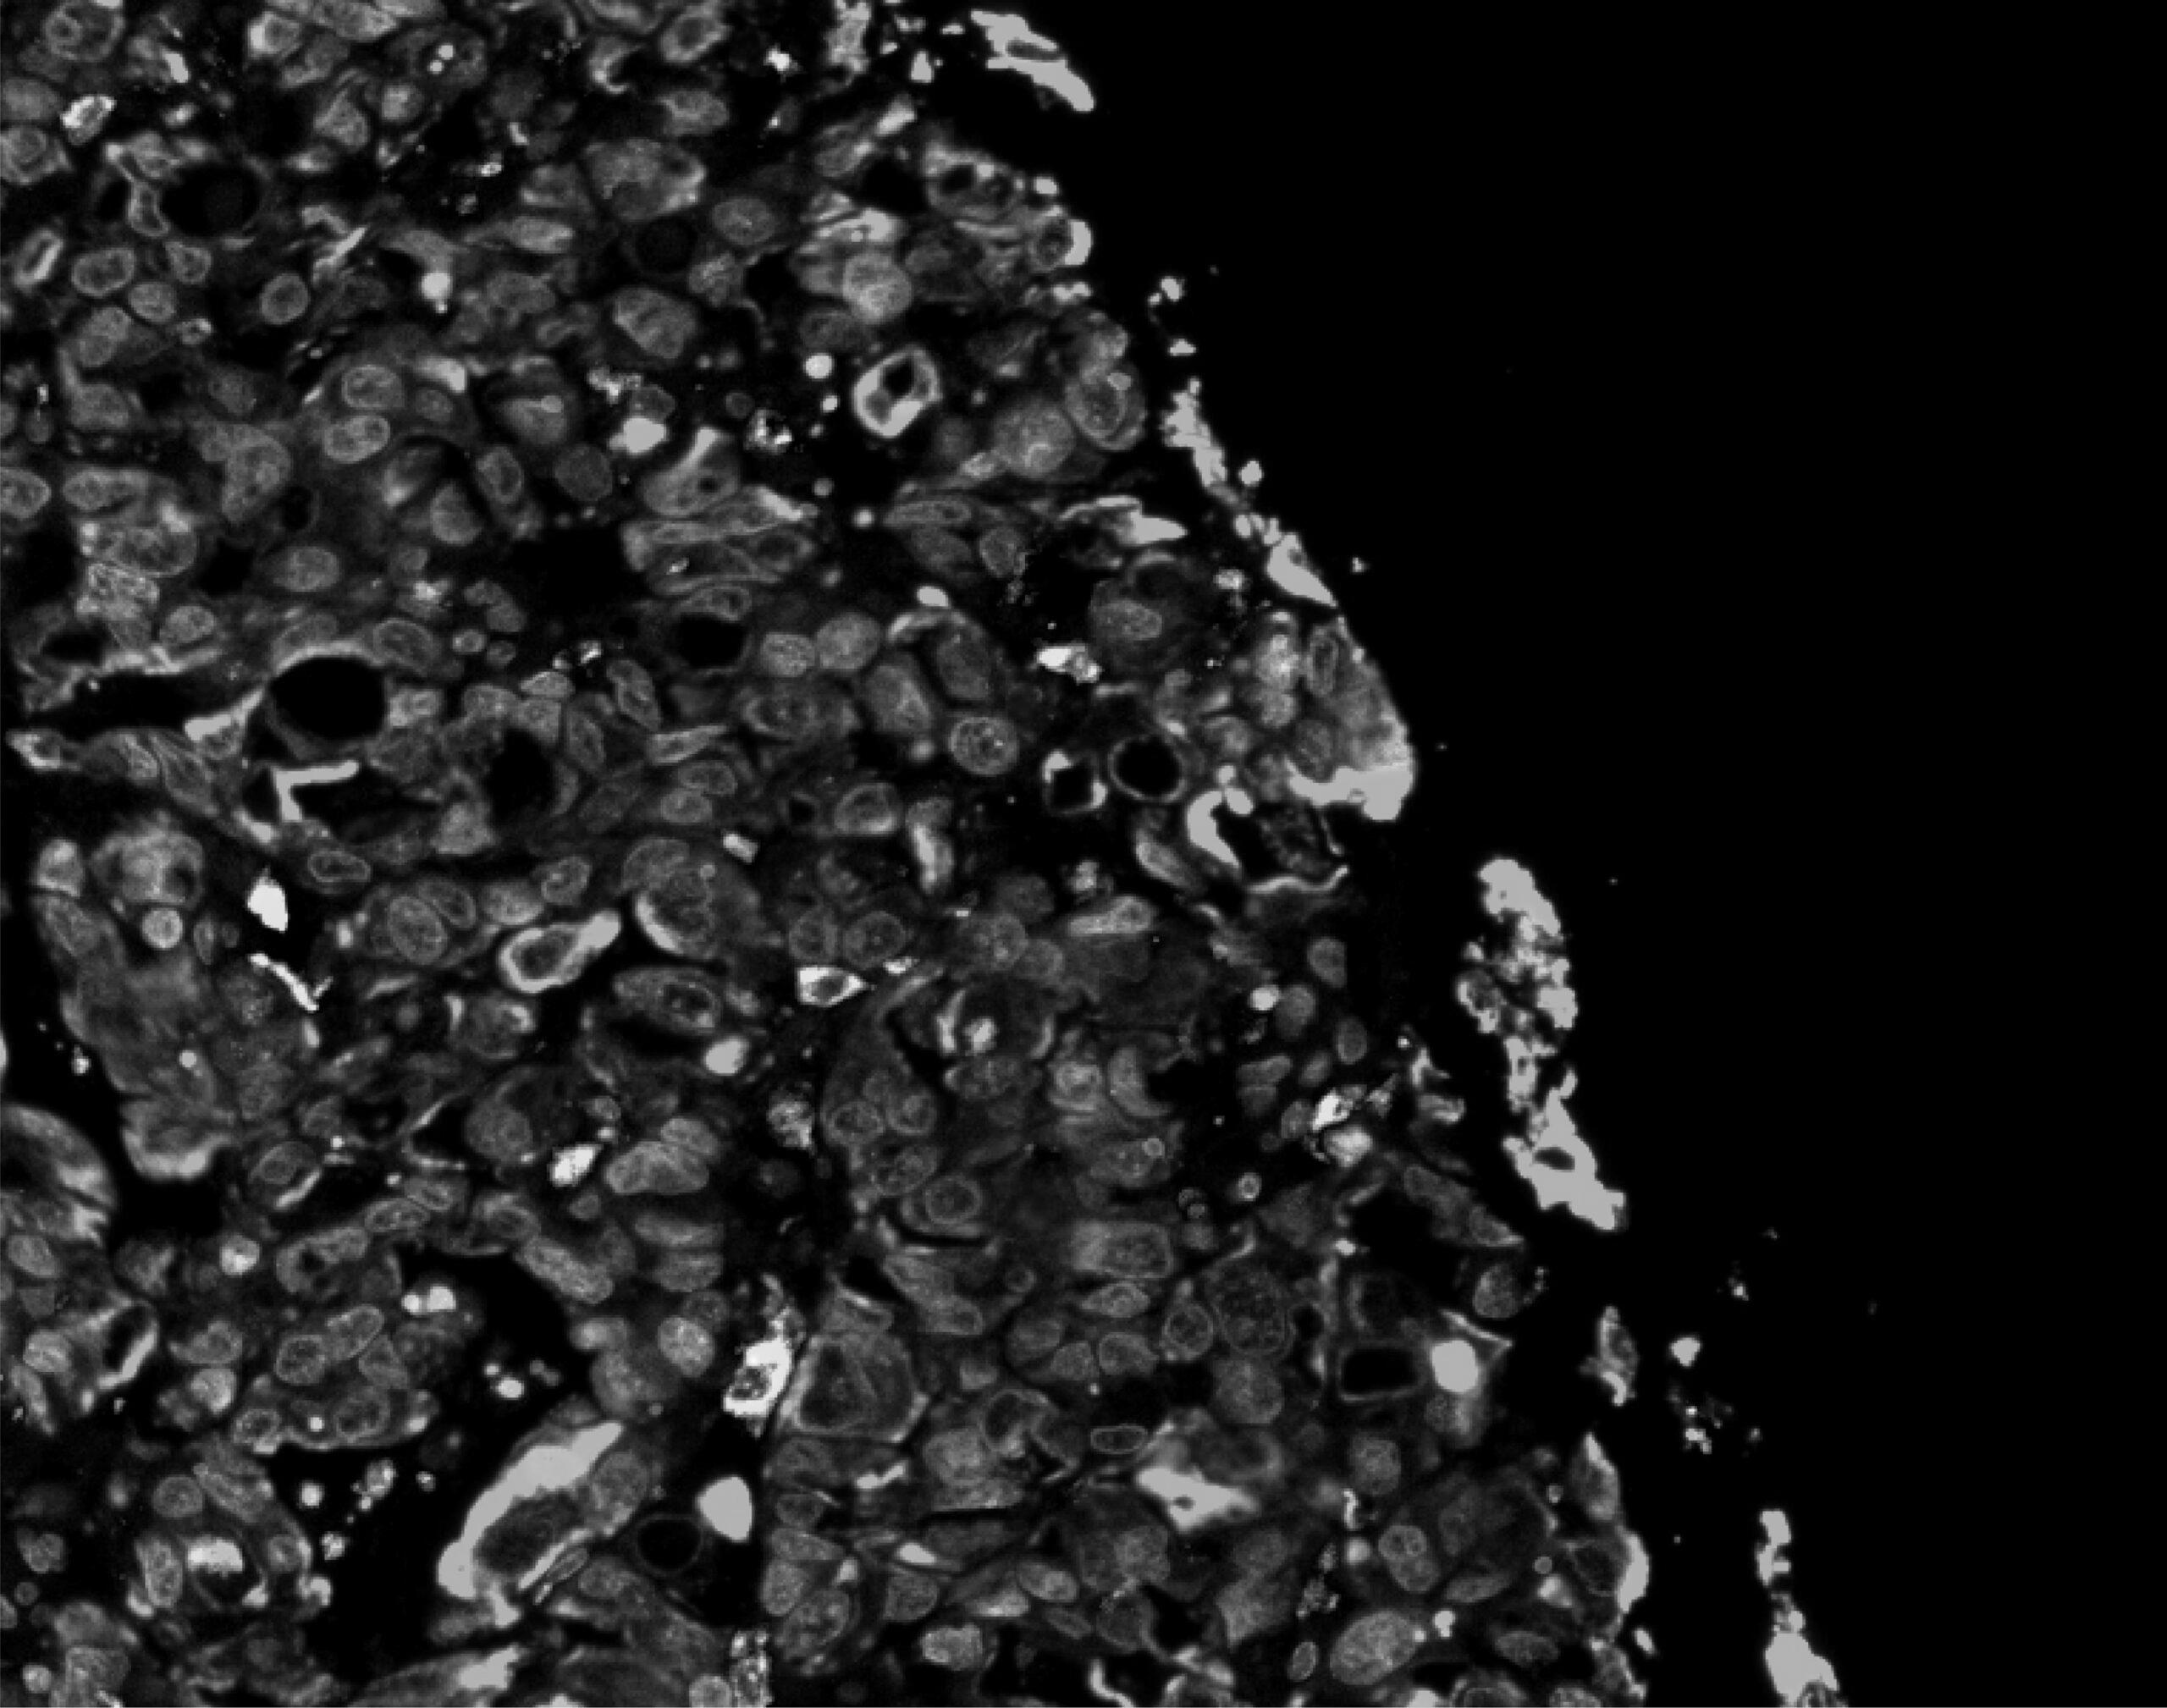

The study, led by Professor Eileen Parkes and her team in the Department of Oncology at the University of Oxford, analysed patient-donated tumour samples and found that the most dangerous types of oesophageal cancers share a key feature: high chromosomal instability. This means the cancer cells constantly make mistakes as they grow and divide, making them more aggressive, harder to treat, and allowing them to adapt more easily.

Using newly developed laboratory models of oesophageal cancer, the researchers found that cancers with unstable chromosomes ‘switch on’ certain genes. These genes were shown to send out chemical signals that attracted inflammatory immune cells into the tumour, bolstering its defence.

The paper, ‘Chromosomal instability shapes the tumor microenvironment of esophageal adenocarcinoma via a cGAS-chemokine-myeloid axis‘, is published in Science Advances.